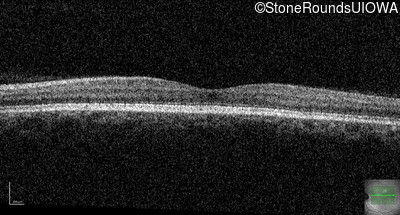

Congenital Stationary Synaptic Dysfunction (IA2g)

Congenital Stationary Synaptic Dysfunction (IA2g)

| Congenital Stationary Synaptic Dysfunction | CABP4 | Arg49Stop CGA>TGA | IVS1+1 G>T | AR |